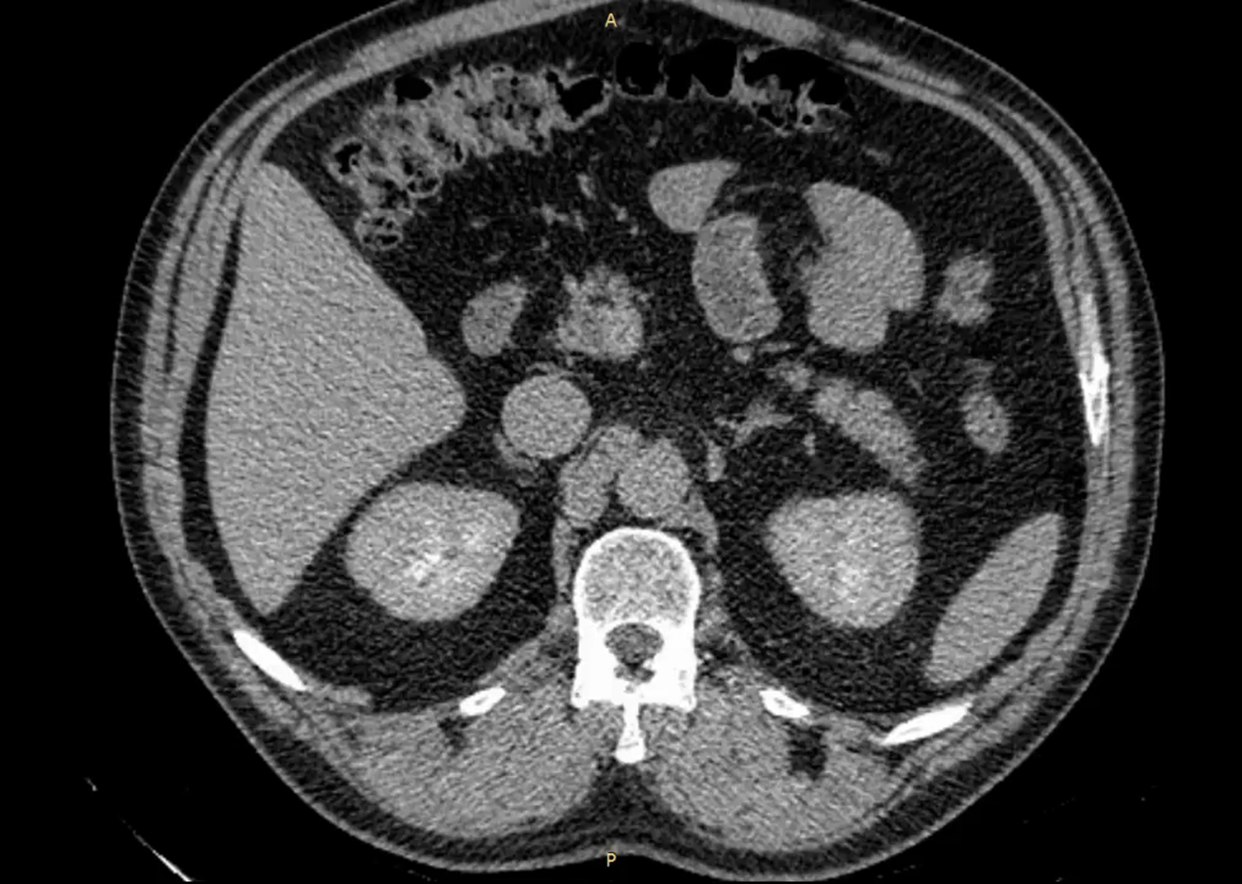

Тогда урологи из МСЧ «Нефтяник» решили провести операцию, которая минимально травмирует сосуды почки. Для этого они изучали КТ-снимки и архитектонику органа.

Фото: Департамент здравоохранения Тюменской области